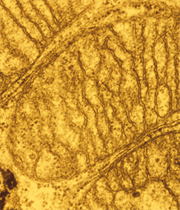

La levadura de cerveza puede utilizarse como modelo para comprender patologías mitocondriales como el síndrome de Leigh, una enfermedad degenerativa del sistema nervioso central que afecta a niños y jóvenes, según una investigación llevada a cabo por un grupo de científicos franceses.

ImagenSe trata del primer modelo farmacológico desarrollado para este tipo de patologías, señaló el Centro Nacional de Investigación Científica de Francia (CNRS), que destacó que los expertos esperan que permita desarrollar tratamientos para tratar el origen genético de las enfermedades y no simplemente sus síntomas.